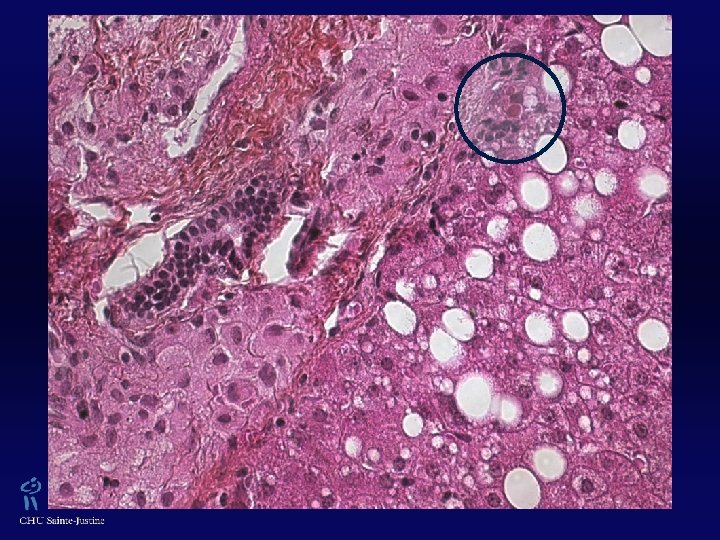

XGJ w Trois types cellulaires : w Cellules mononucléées w Cellules géantes mutinucléées, ± de type cellules de Touton (› lésions cutanées, absentes dans les formes jeunes) w Cellules fusiformes w ± Vacuoles cytoplasmiques, avec aspect xanthomateux w Éosinophiles 0/+++ w Vimentine +, CD 68 +, Facteur XIIa +, Fascine + w Protéine S 100 ± w CD 1 A -, absence de granules de Birbeck (ME)

Histiocytoses non-langerhansiennes XGJ Xanthogranulome juvénile Prolifération cellules dendritiques Histiocytose de Langerhans XGJ Xanthome papuleux Maladie de Rosai-Dorfman etc. Prolifération macrophages Syndromes hémophagocytaires Xanthogranulome juvénile Maladie de Rosai-Dorfman

Proliférations histiocytaires du foie w Population résidente macrophagique w Cellules Kupffer : ↑ nombre, taille, activité suite à divers stimuli locaux ou systémiques (hépatite, sepsis) w Syndrome d’activation macrophagique w Syndromes lymphohistiocytaires héréditaires w Histiocytose de Langerhans w Xanthogranulome juvénile/Xanthome disséminé